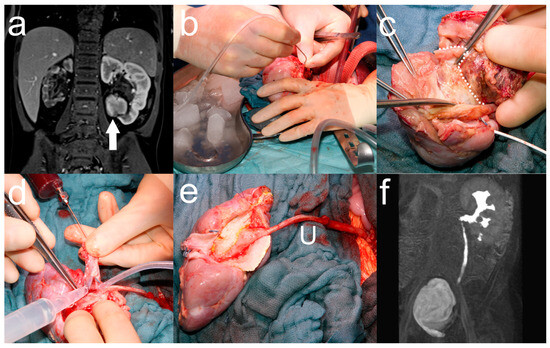

2.2. Ante Situ Tumor Resection and Orthotopic Renal Autotransplantation for Bilateral Nephroblastoma

2.3. Renal Autotransplantation in Neuroblastoma Resection